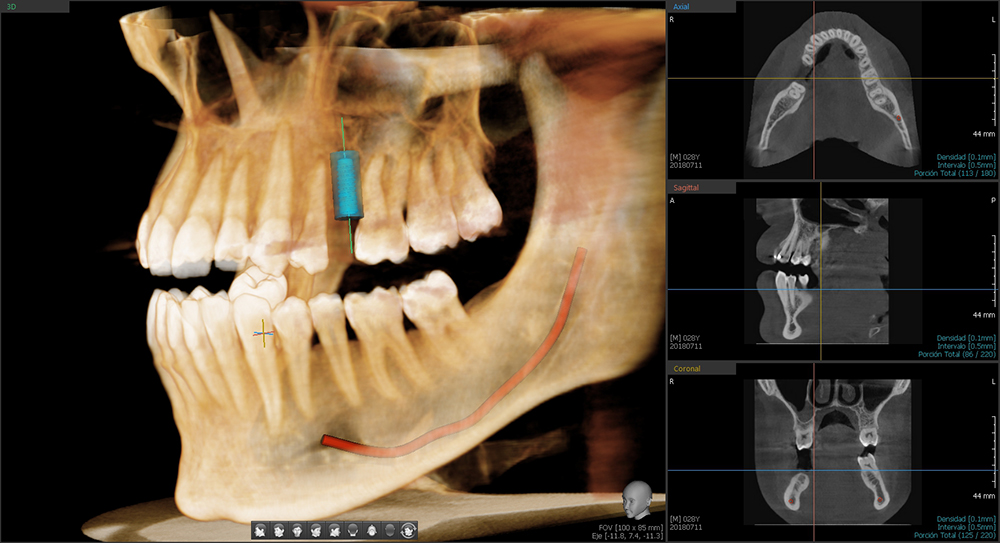

Ortoscan es una cadena de centros radiológicos especializados en ofrecer soluciones personalizadas en diagnóstico por la imagen digital a todos los profesionales que desarrollan su actividad en el área de la boca, la cabeza y el cuello utilizando la mas avanzada y novedosa tecnología digital.

No nos limitamos a suministrar imágenes, ofrecemos asesoramiento en el diagnóstico y la planificación de los casos remitidos, cuidando siempre hasta el último detalle para facilitar al máximo el trabajo de los profesionales.

Somos un centro de diagnóstico especializado. No nos limitamos a suministrar imágenes, ofrecemos asesoramiento en el diagnóstico y la planificación de los casos remitidos con la máxima calidad y servicio impecable, cuidando siempre hasta el último detalle para facilitar al máximo el trabajo de los profesionales.

- Planificación de implantes dentales

- Planificación de implantes dentales

- Planificación de implantes dentales